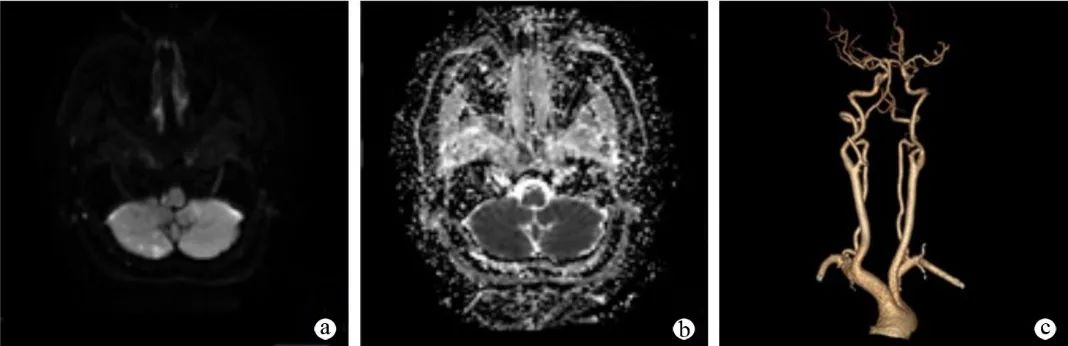

病例三

患者,女,60 岁,因头晕伴左下肢麻木 10 余天入院。既往有高血压史 10 年,神经系统查体:左侧 T10 以下痛觉减退,四肢肌力 V 级,双侧病理征阴性。

a:头颅 MRI 弥散成像序列提示右侧延髓外侧及右侧小脑半球 DWI 高信号病灶;b:右侧延髓外侧及右侧小脑半球 ADC 低信号病灶;c:头颈部 CTA 提示双侧颈内动脉虹吸部、椎动脉颅内段及基底动脉钙斑影,伴管腔粗细不均匀,局部轻度-中度狭窄。